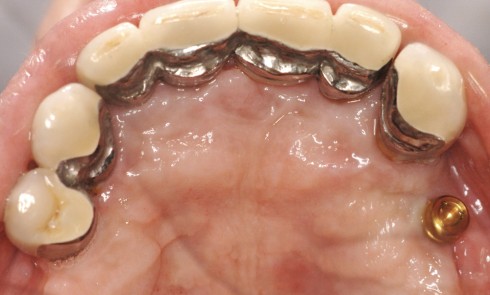

Article réservé à nos abonnés Prothèse amovible partielle combinée : à propos d’un cas clinique

L’apparition et la démocratisation de l’implantologie ont diminué les indications de PAP composite. Toutefois, dans certaines situations, conserver quelques dents...